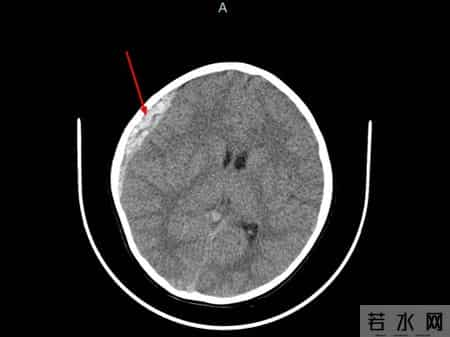

之后,急诊团队迅速为童童完善相关检查,头颅CT检查结果显示:右额顶骨骨折,右侧颞顶部硬膜外血肿,中线结构明显偏移,随时可能发生脑疝。

杭州市儿童医院供图